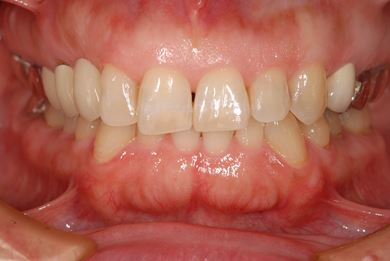

治療前

• 治療前

治療後

• 治療後